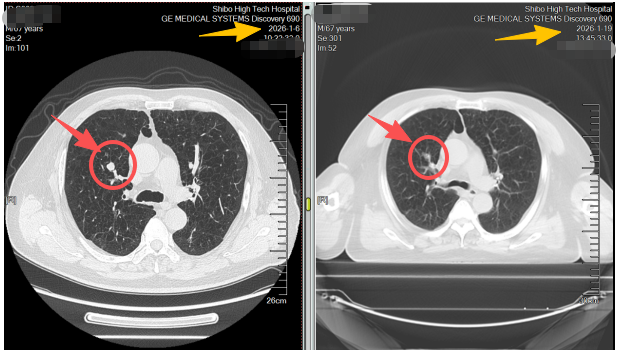

不同于传统放疗需数十次照射、持续一两个月,患者需要数次的射波刀治疗,全程无切口、无出血、无需麻醉,每次治疗约30分钟,结束后即可自主离院。治疗两周后复查CT,影像结果显示:原本的肺结节病灶基本消失,周围正常肺组织无任何损伤,患者身体状态良好,无明显不适症状。